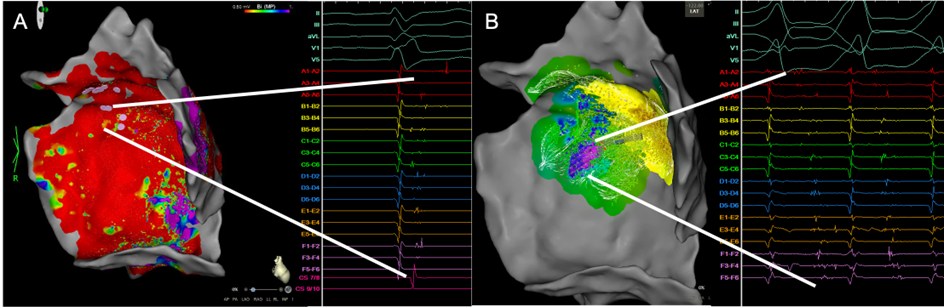

3D-elektroanatomisches Map des epikardialen LV mit Ansicht von endokardial/innen.

Abbildung 2: 3D-elektroanatomisches Map des epikardialen LV mit Ansicht von endokardial/innen. Im Voltage map im Sinusrhythmus (A) zeigte die gesamte laterale Wand des LV low-voltage (0.5mV-1.5mV). Im basalen Anteil der Narbe fanden sich ausgeprägte spätpotentiale (Ansicht von rechts lateral). B: Aktivierungs-Map der VT mit langen, fraktionierten Potentialen aus dieser Region, die sich fast über die gesamte Diastole erstecken.